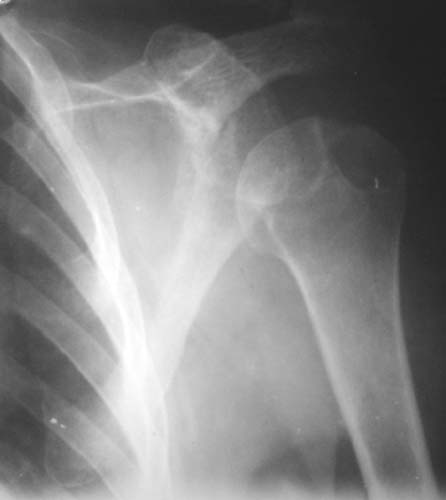

Активное отведение 80 гр., при пальпации - головка плечевой кости безболезненно вправляется и тут же самостоятельно вывихивается. Наложена косыночная иммобилизация, рентгенография (r3) и МРТ.В нашем диагностическом центре МРТ исследование плечевого сустава выполнено впервые, опыта у нас маловато :(.Вопросы: уточнение диагноза? какие исследования провести? тактика лечения?

1

2

"Прицельная" съемка малопонятного очага.

1. На рентгене - нижний подвывих плеча и очаг остеолиза суставного бугорка с четкими контурами (вдавленный перелом на фоне остеопороза ? доброкачественная опухоль? аваскулярный некроз ? (хотя ни разу не слышал об аваскулярном некрозе плеча..)

Судя по снимкам, речь идTт о типичном случае Hill-Sachs Lesion. По этому поводу я позволю себе некоторый экскурс:

97 % всех вывихов плеча происходит по механизму комбинации отведения, разгибания и наружной ротации (А. Гринспан). В момент вывиха головка плеча ударяет о нижний край гленоида, что ведет к вдавленному или компрессионному перелому одной или обеих структур. Чаще всего, однако, повреждение возникает в задней латеральной области головки плечевой кости на переходе от головки к шейке. Этот диагноз можно выставить на основании рентгеновского снимка в переднезадней проекции с внутренней ротацией плеча. Несколько реже видно повреждение гленоида о передненижний перелом края. То, что мы называем Bankart Lesion. Это повреждение видно на ре. снимке в п.з. проекции при нейтральной позиции плеча. Разумеется хрящевые и мягкотканные повреждения (в смысле Банкарт) мы увидим лучше всего на ЯМР.